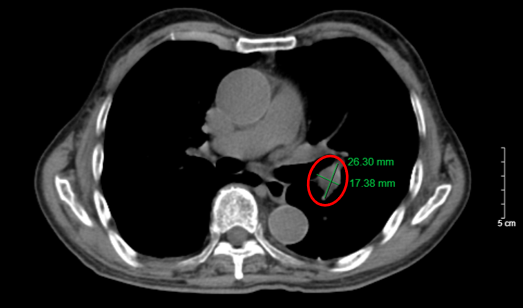

CASE LÂM SÀNG Điều trị bệnh nhân mắc đồng thời hai loại ung thư: Ung thư phổi và ung thư tuyến tiền liệt

CASE LÂM SÀNG Điều trị bệnh nhân mắc đồng thời hai loại ung thư: Ung thư phổi và ung thư...